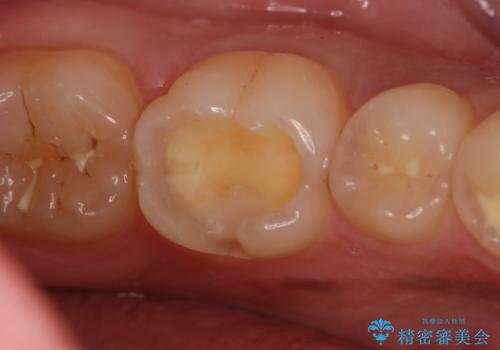

- 左下6番の治療のやり直しを希望し来院された患者様です。

保険の材料が劣化し段差や隙間ができてしまっている状態です。

自費の治療を希望されたため切削量・形態を考慮し、セラミックインレーでの治療を計画しました。